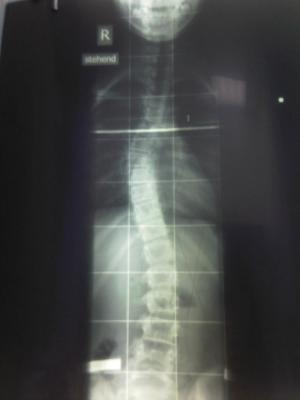

hier nun die röntgen-ergebnisse:

liebe grüße

kessy2cat

vor Behandlung november 2008 - thorakal 33 Grad

<br />                          lumbal 29 Grad

lumbal 29 Grad

thorakal33.jpg (8.42 KiB) 10029 mal betrachtet